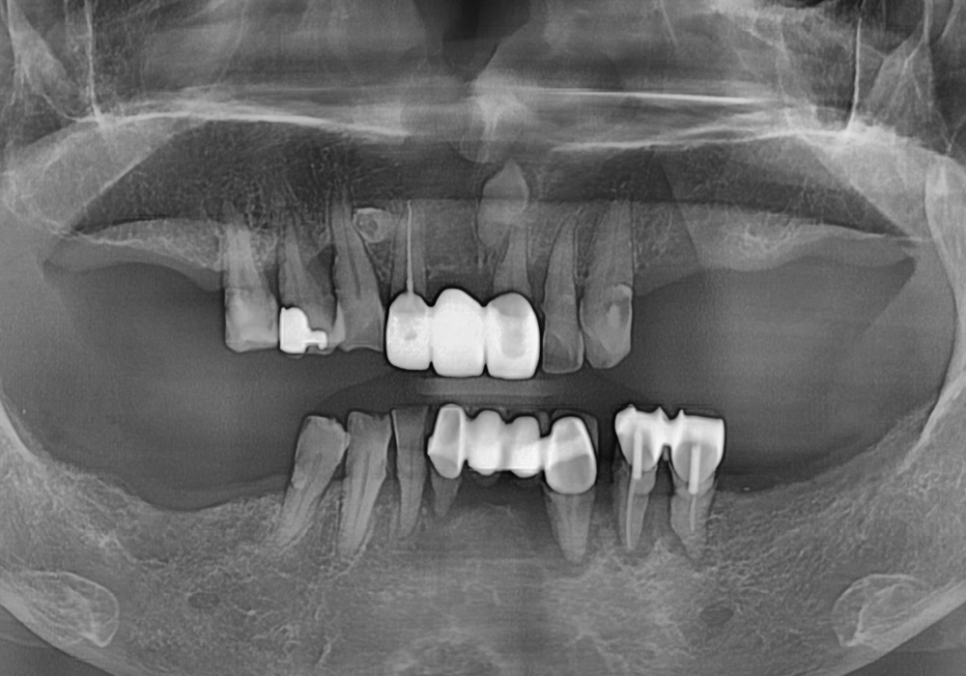

이분은 위아래 부분 틀니를

오랫동안 사용해오셨는데,

어느 순간부터 아래 틀니가 자꾸 들썩거리며

씹는 게 불편하다며 내원하셨어요.

검사 결과, 틀니를 지탱해주던

남은 치아 9개 중 무려 6개가

잇몸 질환으로 인해 심하게 흔들리고 있었습니다.

231023

지지대가 무너졌으니

틀니가 제 역할을 못 하는 것은 당연하겠죠~

환자분과 상의 끝에 안 좋은 치아들을 정리하고

디지털 가이드를 활용해

총 7대의 임플란트를 심어

아래 전체 치아를 재건하기로 했습니다.